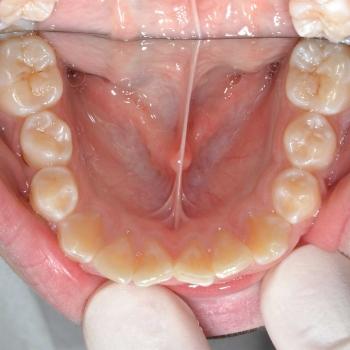

Gergő és édesanyja fogorvosi javaslatra keresett fel, a bal felső 2. kisőrlő hibás pozíciója miatt. A konzultáció során egyértelművé vált, hogy az előbb említett fog helyét teljes mértékben elfoglalták az előtte, illetve mögötte elhelyezkedő fogak, gyakorlatilag 0mm helyet hagyva a probléma megoldására. Ilyen esetekben felmerül a szájpadi irányba kiszorult fog eltávolítása, de a felső fogívben tapasztalható résesség a helyteremtés mellett szólt.

A kezelés első lépéseként Frog készülékkel hátrafelé mozdítottuk a bal felső első nagyőrlőt, ezzel elrendezve a nagyőrlők érintkezését, másfelől 4mm helyet teremtve a második kisőrlő számára. Ez a hely még nem volt elegendő, így rögzített fogszabályozóval zártuk a nagymetszők közötti, illetve az első kisőrlő előtti rést, mellyel további 2.5mm helyet nyertünk. Az így már 6.5mm-es rés elegendő volt ahhoz, hogy a kiszorult kisőrlőt bemozdítsuk a kívánt pozícióba, ezzel kialakítva egy funkcionálisan megfelelő és esztétikus felső fogívet. Mivel a harapás korrekciója, azaz a funkció helyreállítása kizárólag a felső fogív kezelésével is kivitelezhető volt, így a szülők nem kérték az alsó fogív torlódásának a megoldását.

A kezelés teljes időtartama: 2 év